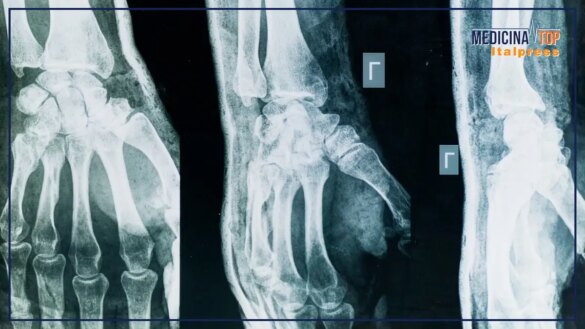

La riflessione di Selmi si sofferma su due aspetti: riconoscimento della malattia e fattori di rischio. “La diagnosi di artrosi si fa tuttora con la semplice radiografia; il consumo di cartilagine di uno dei due capi ossei porta un avvicinamento delle due ossa all’interno dell’articolazione e si ha l’artrite reumatoide, che può essere intercettata prima e trattata con efficacia. La prima localizzazione tipica dell’artrosi è la schiena: se facciamo una radiografia della colonna lombare o cervicale a chiunque abbia più di cinquant’anni troveremo segni di artrosi in tutti, ma per fortuna non tutti ne soffrono; dopo la localizzazione della colonna si passa alle mani. I fattori di rischio più importanti sono per l’artrosi familiarità, genere femminile, età avanzata e sovrappeso, indipendentemente dalla localizzazione; per l’artrite reumatoide familiarità, genere femminile e fumo di sigaretta; per l’artrite psoriasica la presenza di psoriasi”.